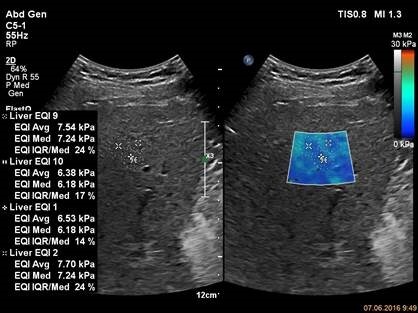

Для исследования используется прибор EPIQ 7, датчик С5-1, приложение ElastQ и карта надежности. Карта надежности исследования позволяет достоверно выбрать участок печени в котором боковые волны имели максимальную интенсивность. Измерение в данном участке печени будет иметь минимальную вариабельность.